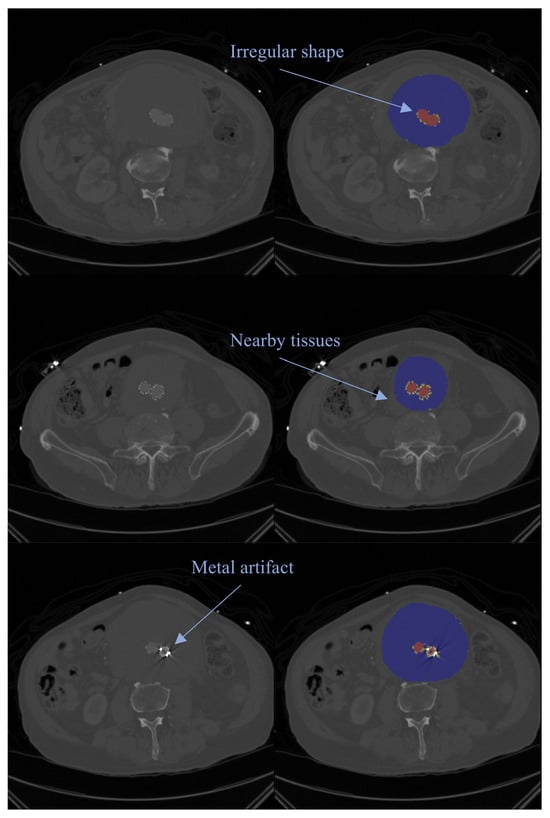

Open AccessArticle

Real-World Evaluation of an AI-Assisted Diagnostic Support System for Early Gastric Cancer: Diagnostic Performance, Confidence Stratification, and Determinants of False-Positive Diagnosis

by

Satoshi Osawa, Takanori Yamada, Wataru Inui, Tomoyuki Niwa, Kenichi Takahashi, Takatoshi Egami, Keisuke Inagaki, Tomohiro Takebe, Tatsuhiro Ito, Satoru Takahashi, Shunya Onoue, Yusuke Asai, Kiichi Sugiura, Tomoharu Matsuura, Natsuki Ishida, Mihoko Yamade, Moriya Iwaizumi, Yasushi Hamaya and Ken Sugimoto

J. Clin. Med. 2026, 15(7), 2609; https://doi.org/10.3390/jcm15072609 (registering DOI) - 29 Mar 2026

Abstract

Background/Objectives: Artificial intelligence (AI)-assisted endoscopy has shown high sensitivity for early gastric cancer detection; however, false-positive diagnoses remain a clinical challenge. This study aimed to evaluate the real-world diagnostic performance of a commercially available AI system and to identify factors associated with

[...] Read more.

Background/Objectives: Artificial intelligence (AI)-assisted endoscopy has shown high sensitivity for early gastric cancer detection; however, false-positive diagnoses remain a clinical challenge. This study aimed to evaluate the real-world diagnostic performance of a commercially available AI system and to identify factors associated with false-positive diagnoses, focusing on repeated AI evaluations and confidence stratification. Methods: This single-center retrospective study included 47 patients with 89 localized gastric lesions evaluated between March 2024 and March 2025. Endoscopic examinations were performed under white-light, non-magnified observation with repeated AI assessments of each lesion. The rates of “Consider biopsy” (B) judgments were calculated. Lesions with a B judgment rate of ≥50% were defined as AI-positive and classified into four AI confidence categories. Diagnostic performance was assessed using sensitivity, specificity, positive predictive value (PPV), and negative predictive value (NPV). Factors associated with false-positive diagnoses were analyzed using penalized logistic regression. Results: The AI system demonstrated a sensitivity of 97.6% and an NPV of 95.7%, with a specificity of 45.8%. Pathology-positive rates decreased stepwise across the four AI confidence categories (p < 0.001). Among AI-positive lesions, low regional reproducibility, lesion size ≥ 30 mm, scar, and erosion were independently associated with false-positive diagnoses. In analyses restricted to non-neoplastic lesions, lesion size ≥ 30 mm remained significantly associated with false-positive diagnosis. Conclusions: In real-world clinical practice, a commercially available AI system provides high sensitivity for early gastric cancer detection. Incorporating confidence stratification and regional reproducibility into clinical decision-making may enhance the effective use of AI-assisted endoscopic diagnosis beyond binary interpretations.

Full article

(This article belongs to the Special Issue Endoscopic Innovations in Gastrointestinal Diseases: From Diagnosis to Therapy)